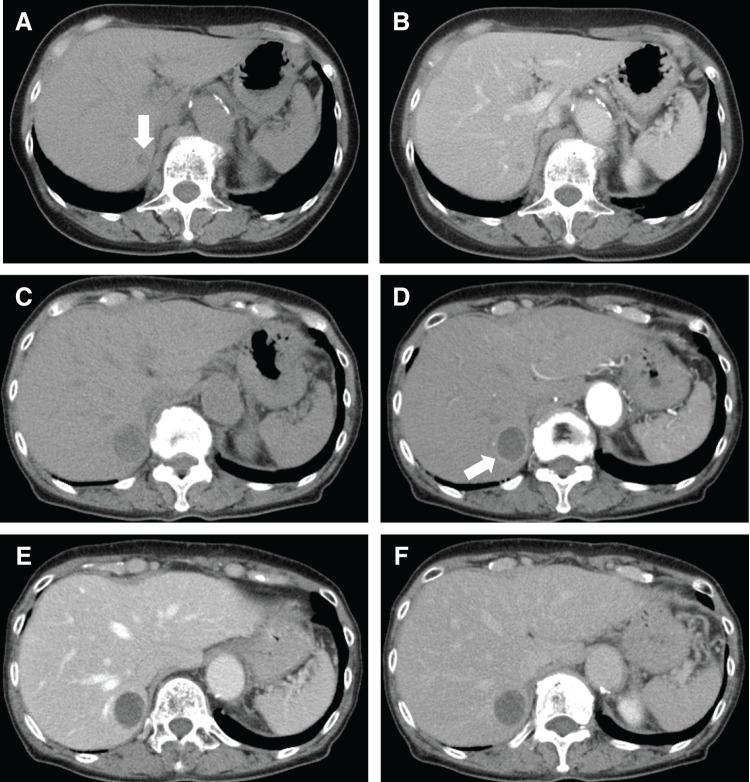

A woman in her 70s with no history of chronic liver disease had previously undergone surgery for lung adenocarcinoma and for localized nodular hyperplasia of the liver. Routine follow-up imaging revealed an enlarging liver mass in the right hepatic lobe, leading to her referral for further evaluation. Tumor markers were within normal ranges, and liver function remained intact. Non-contrast CT showed a low-attenuation nodule, and contrast-enhanced CT demonstrated ring-like peripheral enhancement with a hypovascular center. Magnetic resonance imaging showed low signal on T1-weighted images and high signal on T2-weighted images, with no signal loss in opposed-phase imaging. Ultrasonography demonstrated a low echogenicity within the tumor and high echogenicity in the surrounding area, with no clear contrast effect. The preoperative diagnosis suggested either a hematoma or a necrotic nodule. Given the progressive growth and inconclusive imaging, malignancy could not be excluded. A laparoscopic hepatectomy was performed for definitive diagnosis. The resected tumor was a 2.3 × 2.0 × 1.4 cm well-demarcated, light brown mass with areas of hemorrhage and cystic change. Histopathology confirmed hepatic AML with tumor hemorrhage and extramedullary hematopoiesis.

一名70多岁的女性,无慢性肝病病史,此前曾接受过肺腺癌及肝脏局灶性结节性增生手术。常规随访影像学检查发现右肝叶有一不断增大的肝脏肿块,遂转诊进行进一步评估。肿瘤标志物在正常范围内,肝功能保持正常。非增强CT显示一个低密度结节,增强CT显示周边环形强化,中心血供较少。磁共振成像显示T1加权像上呈低信号,T2加权像上呈高信号,同反相位成像无信号丢失。超声检查显示肿瘤内部呈低回声,周边呈高回声,无明显对比效应。术前诊断提示为血肿或坏死结节。鉴于肿瘤不断生长且影像学表现不明确,不能排除恶性肿瘤的可能。为明确诊断,进行了腹腔镜肝切除术。切除的肿瘤为一个2.3×2.0×1.4 cm的边界清晰、浅棕色肿块,有出血和囊性变区域。组织病理学证实为肝AML伴肿瘤出血和髓外造血。